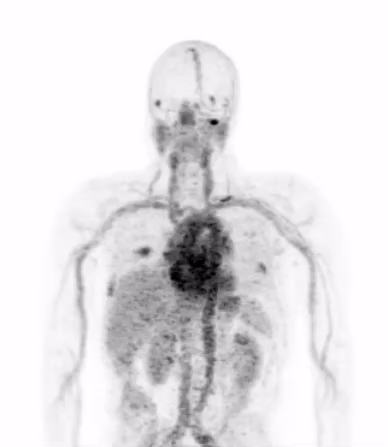

Dr. Evans and his collaborators, most notably Drs. Rahul Aggarwal and Eric Small of the Genitourinary Oncology Service, and Dr. Spencer Behr of the Department of Radiology and Biomedical Imaging, conducted the first study in patients showing that prostate cancer metastases can be imaged with a new PET scan designed to detect only those metastases that are driven by a notorious cancer driver called “MYC”.

These considerations motivated Dr. Evans and his colleagues to propose that a PET scan that could specifically “light up” cancer cells with hyperactive MYC would be the ideal alternative diagnostic tool to study a patient’s cancer biology in the advanced stages in which biopsy is essentially not performed.

Dr. Evans notes that this technology is timely because “new therapies that suppress MYC are entering clinical trials now at UCSF and other centers for the treatment of prostate cancer and other MYC driven cancers. New experimental therapies are nearly always evaluated in patients that have failed standard treatments and as a result have very advanced cancer. These are precisely the patients to which biopsy cannot be easily applied, and for which a “PET biopsy” is most urgently needed. The new PET scan my colleagues and I developed will allow us to identify which patients have tumors with hyperactive MYC, and this in turn will identify those most likely to respond to drugs that inhibit MYC.”